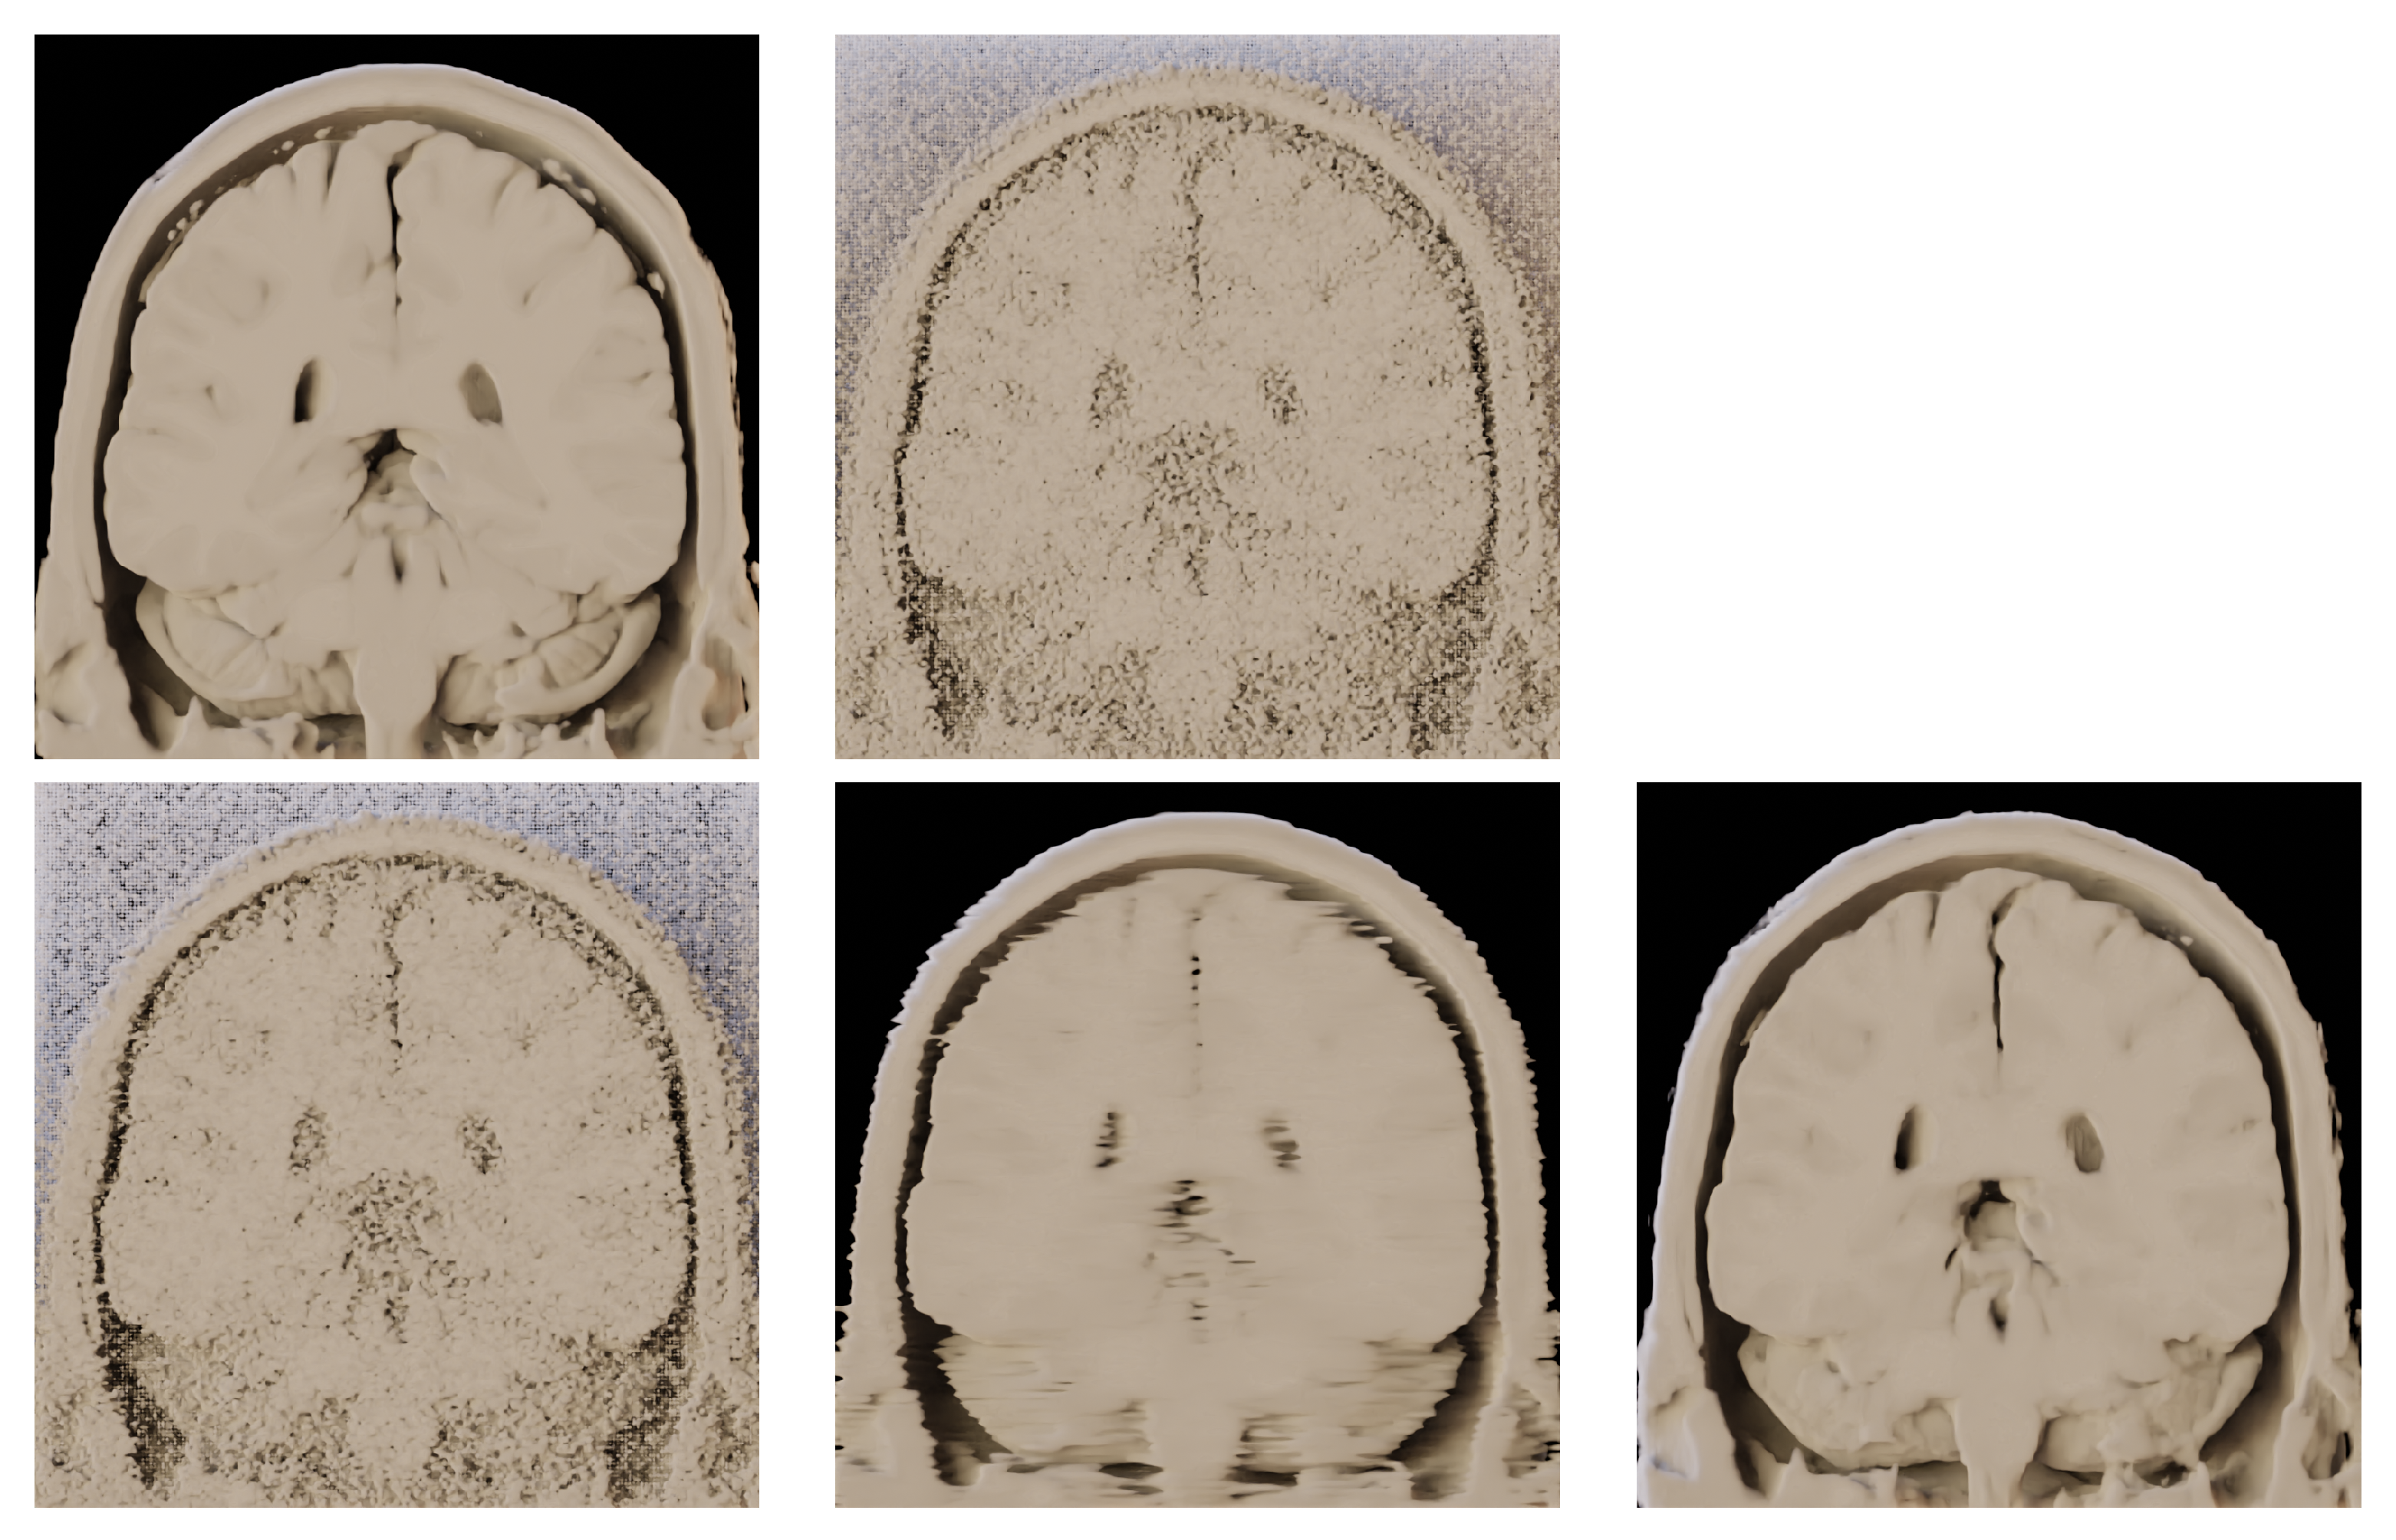

- Comparison of the algorithm with DL-based approaches.

- Testing the algorithm as a pre-processing stage before volume rendering.